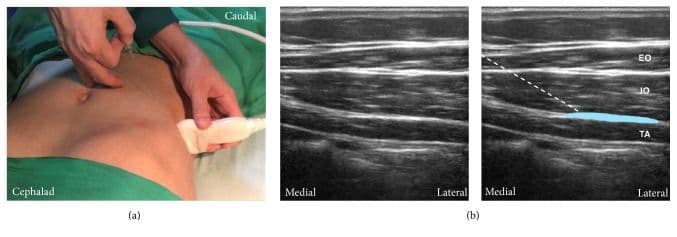

Субкостальний ТАР-блок

Лінійний датчик розміщують вздовж нижнього краю грудної клітки якомога медіальніше та краніальніше. M. rectus abdomini та його задня сполучнотканинна піхва візуалізуються разом з m. transversus abdominis [5,6,13,25].

Цільовою є фасціальна площина між задньою сполучнотканинною піхвою m. rectus abdominis та m. transversus abdominis. Голку вводять вище прямого м'яза живота близько до середньої лінії та просувають у латеральному напрямку. Ціллю ін'єкції є поширення місцевого анестетика між задньою сполучнотканниною піхвою прямого м'яза живота та переднім краєм поперечного м'яза живота [5,6,13,25].